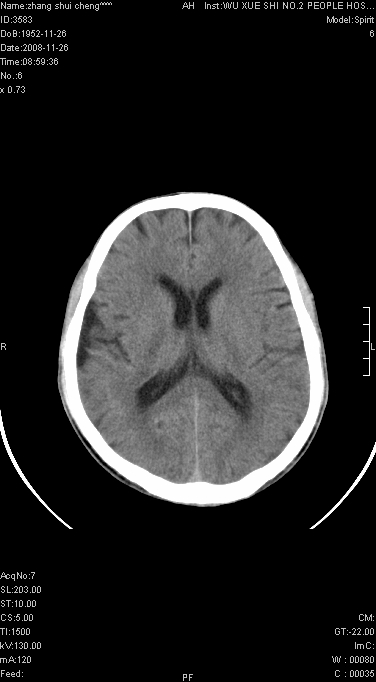

男.68.肢体无力多年

请问是蛛网膜囊肿.还是软化灶.原有中风

脑外性,蛛网膜囊肿

支持右侧颞区蛛网膜囊肿。

蛛网膜囊肿,软化灶周围脑沟应该受牵拉,扩大